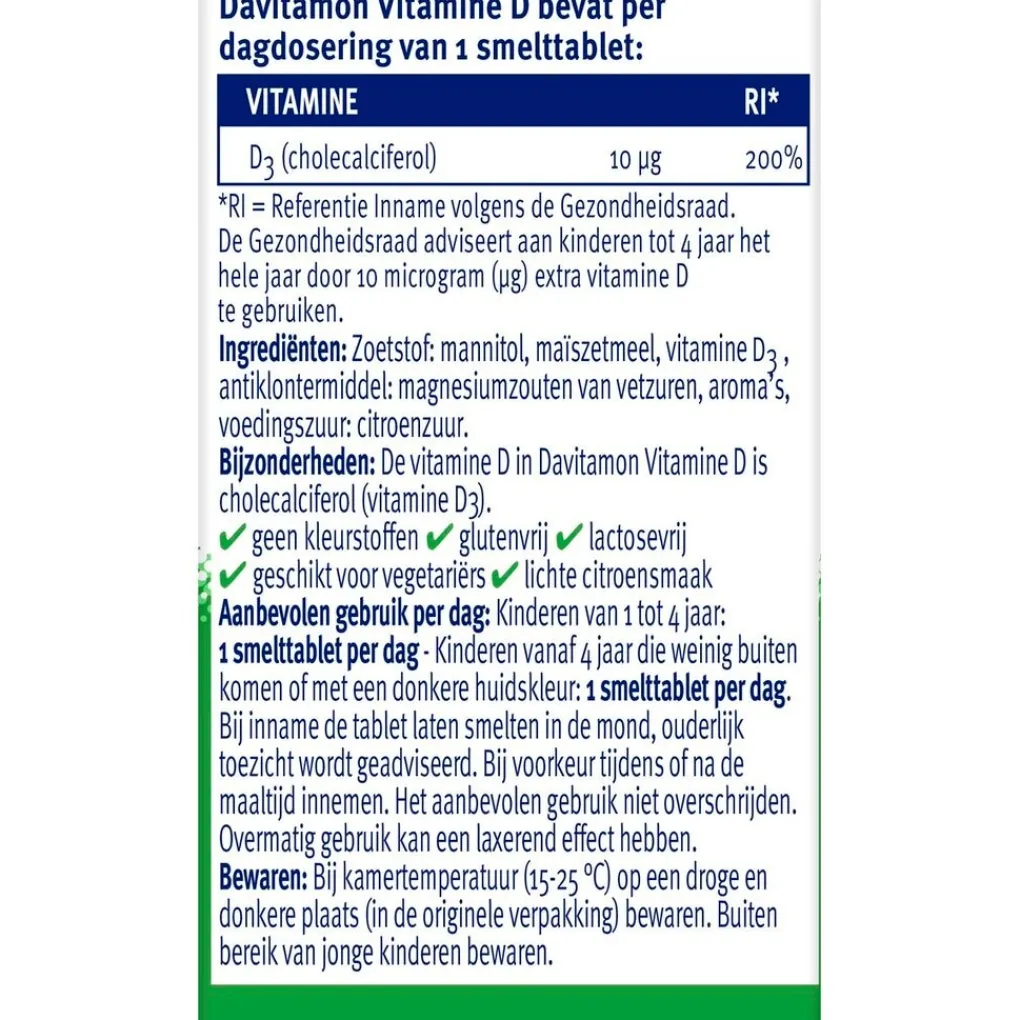

Ingrediënten: zoetstof: mannitol, maïszetmeel, vitamine D3, antiklontermiddel: magnesiumzouten van vetzuren, aroma’s, voedingszuur: citroenzuur.

Een gezonde levensstijl is belangrijk, evenals een gevarieerde, evenwichtige voeding, waarvoor voedingssupplementen geen vervanging zijn. Overmatig gebruik kan een laxerend effect hebben.

Aanbevolen dosering

Kinderen van 1 tot 4 jaar: 1 smelttablet per dag.

Kinderen vanaf 4 jaar die weinig buiten komen of met een donkere huidskleur: 1 smelttablet per dag.

Bij inname de tablet laten smelten in de mond, ouderlijk toezicht wordt geadviseerd.

Bij voorkeur tijdens of na de maaltijd innemen. Het aanbevolen gebruik niet overschrijden.

Samenstelling

Samenstelling:# Davitamon Vitamine D bevat per dagdosering van 1 smelttablet:#Vitamine;

; ;RI*# D3 (cholecalciferol);10;µg;200%# *RI=Referentie Inname volgens de Gezondheidsraad.

Voor kinderen vanaf 1 jaar.

Gebruikers- en bewaarinstructies voor consumenten

Bij kamertemperatuur (15-25 °C) op een droge en donkere plaats (in de originele verpakking) bewaren. Buiten bereik van jonge kinderen bewaren.